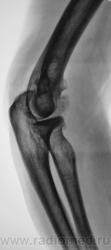

Пациент направлен на рентгенографию локтевого сустава. Была травма или не была не помнит. Пациент весьма пьющий, направлен хирургом с диагнозом "перелом". Рука в локтевом суставе полность не разгибается.

Ваше мнение уважаемые коллеги?

Наверно, застарелый перелом в области блока плечевой кости. Не понятен периостит.